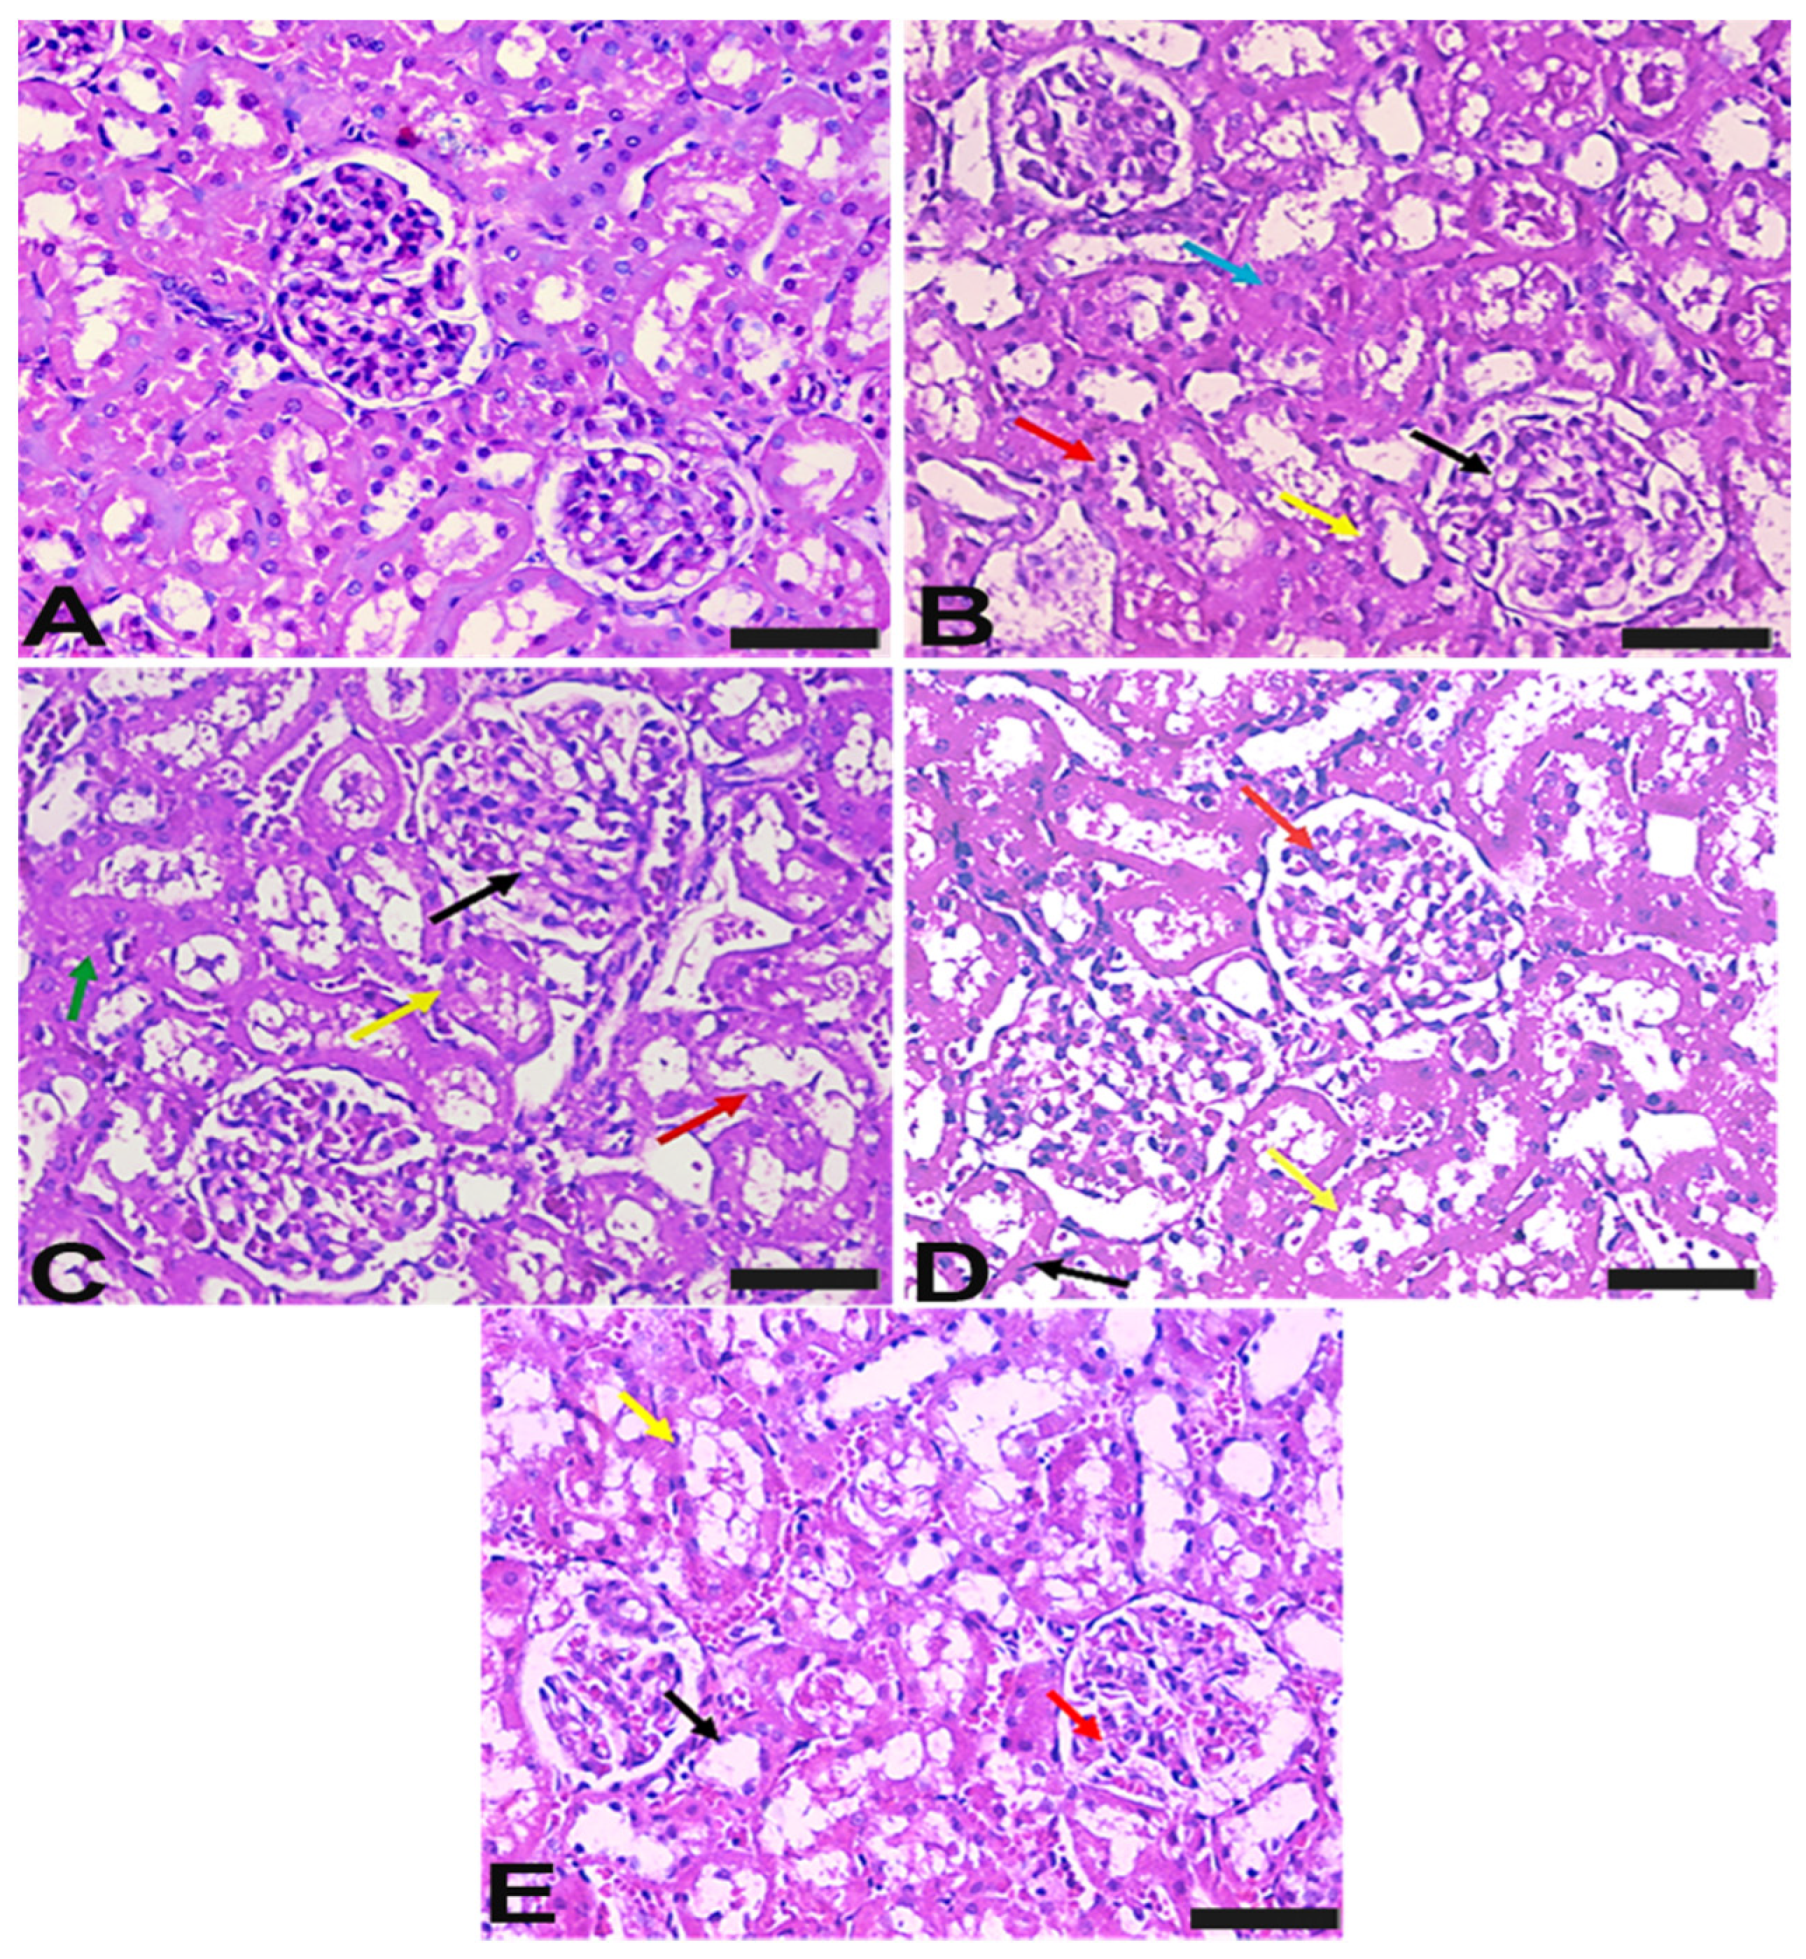

2.7. Vit-E and Lac-B Ameliorated HgCl2 Induced Histopathological Changes in Renal Tissue